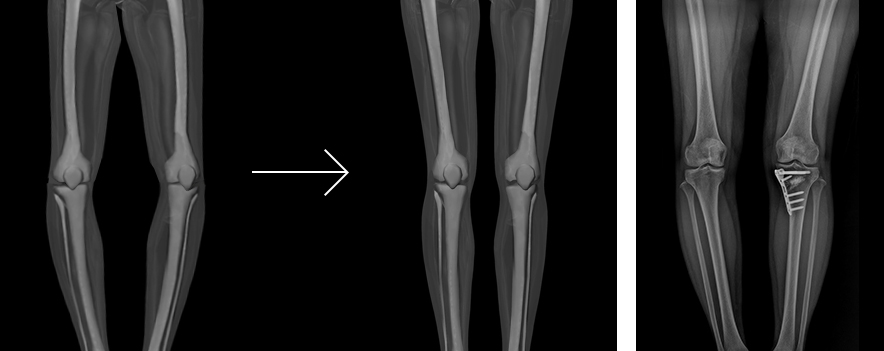

중기 이상의 관절염으로 무릎에 통증이 있거나 관절 손상을 입은 젊은 환자에게 적합한 치료로, 휜 다리(안짱다리)를 원래 모양으로 펴주는 수술입니다. 대개는 휜다리의 관절 안쪽이 닳아져 있기 때문에 다리를 똑바로 펴서 무릎 내측과 바깥쪽에 체중부하를 분산시킴으로써 자기의 관절을 쓸 수 있게 하는 방법입니다.

수술 중 컴퓨터 네비게이션으로 확인하면서 디테일하게 교정해 다리를 곧게 만드는 노하우가 중요합니다. 이렇게 함으로써 인공관절을 하지 않고 다리 관절운동 범위도 정상적으로 유지할 수 있습니다.